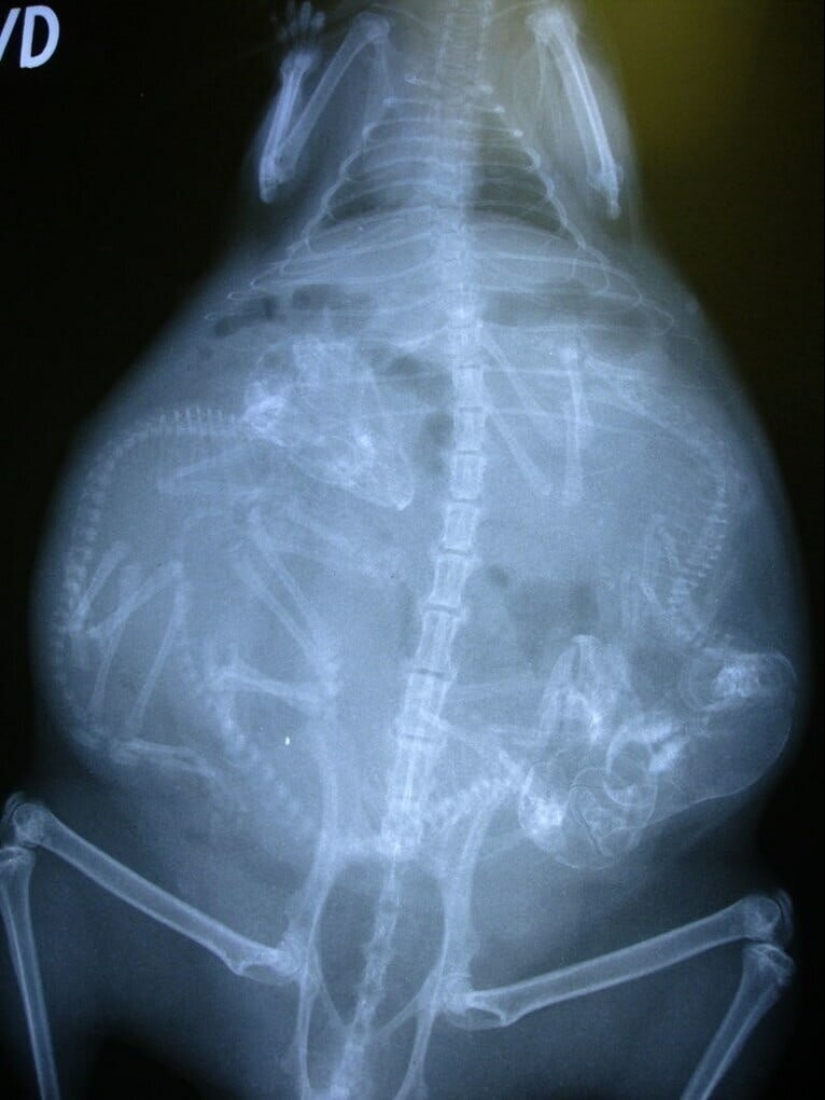

perra preñada